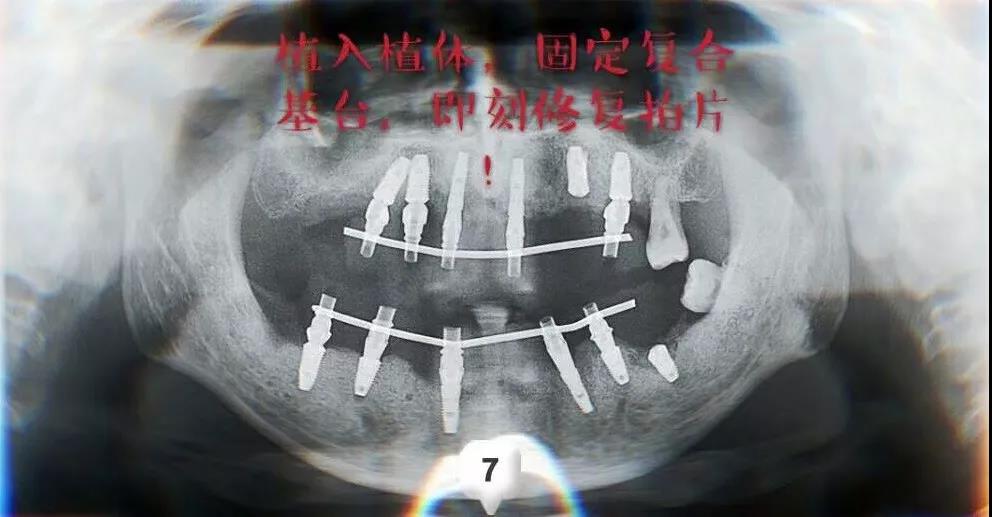

圣洁口腔永兴路院种植科的曹金峰主任为贾先生制定了即拔即种的种植方案,在拔除患牙的同时植入种植体,采用ALL-ON-6全口种植技术配合3D打印技术和数字化种牙导板,全口种植加上即刻负重,是非常有效的牙列重建方案。

经过一周的恢复时间,进行了下半口的种植,曹主任联合种植体加工厂的技师赶工制作完成了全口无牙颌的即刻修复,历时12个小时,手术结束时已经是晚上10点多,患者又开车赶回了北京。

即刻种植即刻修复方案,保障贾先生能正常进食软食,恢复牙齿齐整时的原始面貌,待安装上永久性的种植牙冠便可恢复正常咀嚼功能、正常负重了。